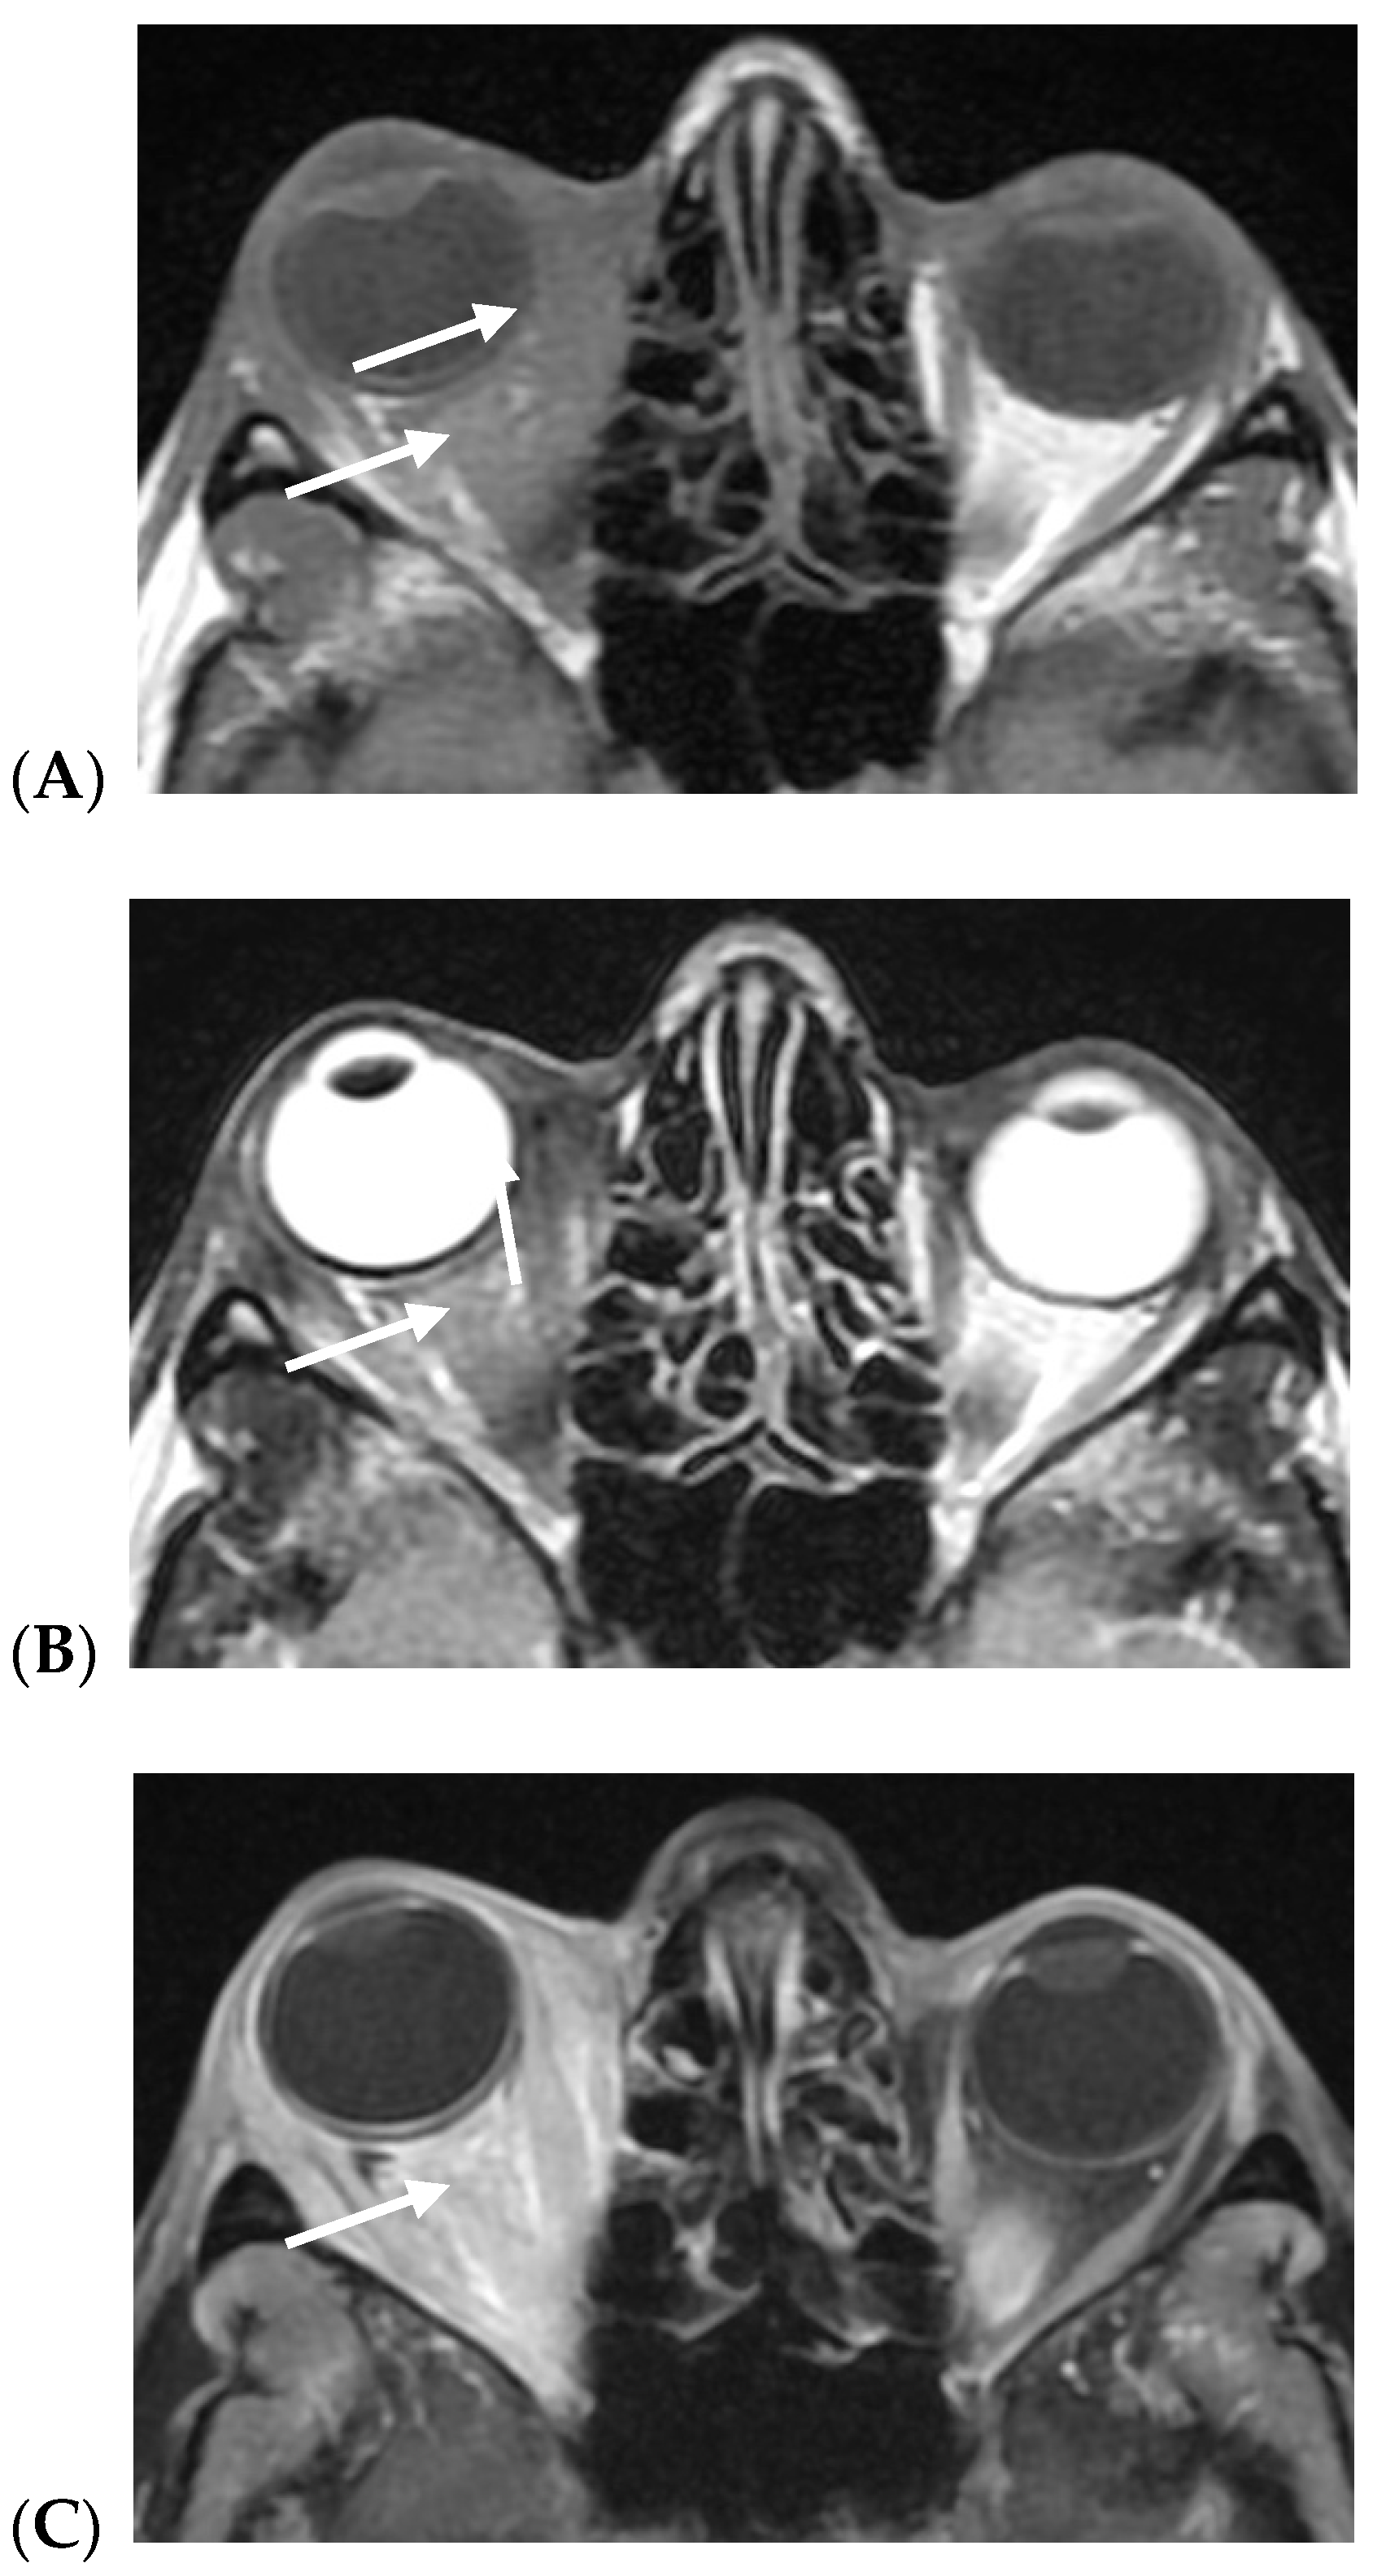

- Russo, C.; Strianese, D.; Perrotta, M.; Iuliano, A.; Bernardo, R.; Romeo, V.; Ugga, L.; Brunetti, L.; Tranfa, F.; Elefante, A. Multi-parametric magnetic resonance imaging characterization of orbital lesions: A triple blind study. Semin. Ophthalmol. 2020, 35, 95–102. [Google Scholar] [CrossRef]